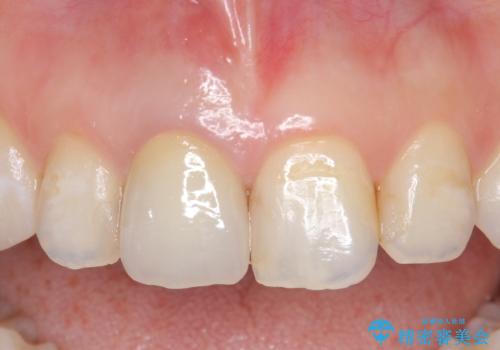

その後オールセラミッククラウン(スペシャル)による補綴を行いました。

前歯の補綴ではオールセラミッククラウンを希望される患者様が多いですが、オールセラミッククラウンの中でも、エコノミー、スタンダード、スペシャル、エクセレントとランクがあります。

その中でも特に審美性が高いのがスペシャル、エクセレントです。スペシャル、エクセレントは口腔内写真をもとに熟練の技工士が、患者様の口腔内に合わせたオーダーメイドのクラウンを製作致します。

今回用いたオールセラミッククラウンはジルコニアフレームという白い素材の上にセラミックを盛っているため、審美性が非常に高いのが特徴です。

また、ジルコニアは人工ダイヤモンドの材料にも使われているほど高い強度を持っており、そのためオールセラミッククラウンは審美性だけでなく、奥歯やブリッジの補綴も可能とするクラウンです。